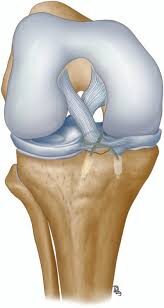

ACL avulsion fixation is a surgical procedure aimed at restoring stability and functionality to the knee joint following an anterior cruciate ligament (ACL) avulsion injury. An ACL avulsion occurs when the ligament tears away from its attachment point on the femur (thigh bone) or tibia (shin bone), often resulting from sudden trauma or excessive stress on the knee. ACL avulsion fixation involves reattaching the torn ligament to its anatomical insertion site using specialized techniques and fixation devices. Let’s delve into the details of ACL avulsion fixation, its surgical approach, and postoperative considerations.

The ACL is a crucial ligament that stabilizes the knee joint by preventing excessive forward movement of the tibia and rotational instability. An ACL avulsion injury occurs when the ligament is torn away along with a fragment of bone from its attachment point. This injury can lead to significant knee instability, pain, swelling, and functional limitations, particularly during activities involving cutting, pivoting, or sudden changes in direction.